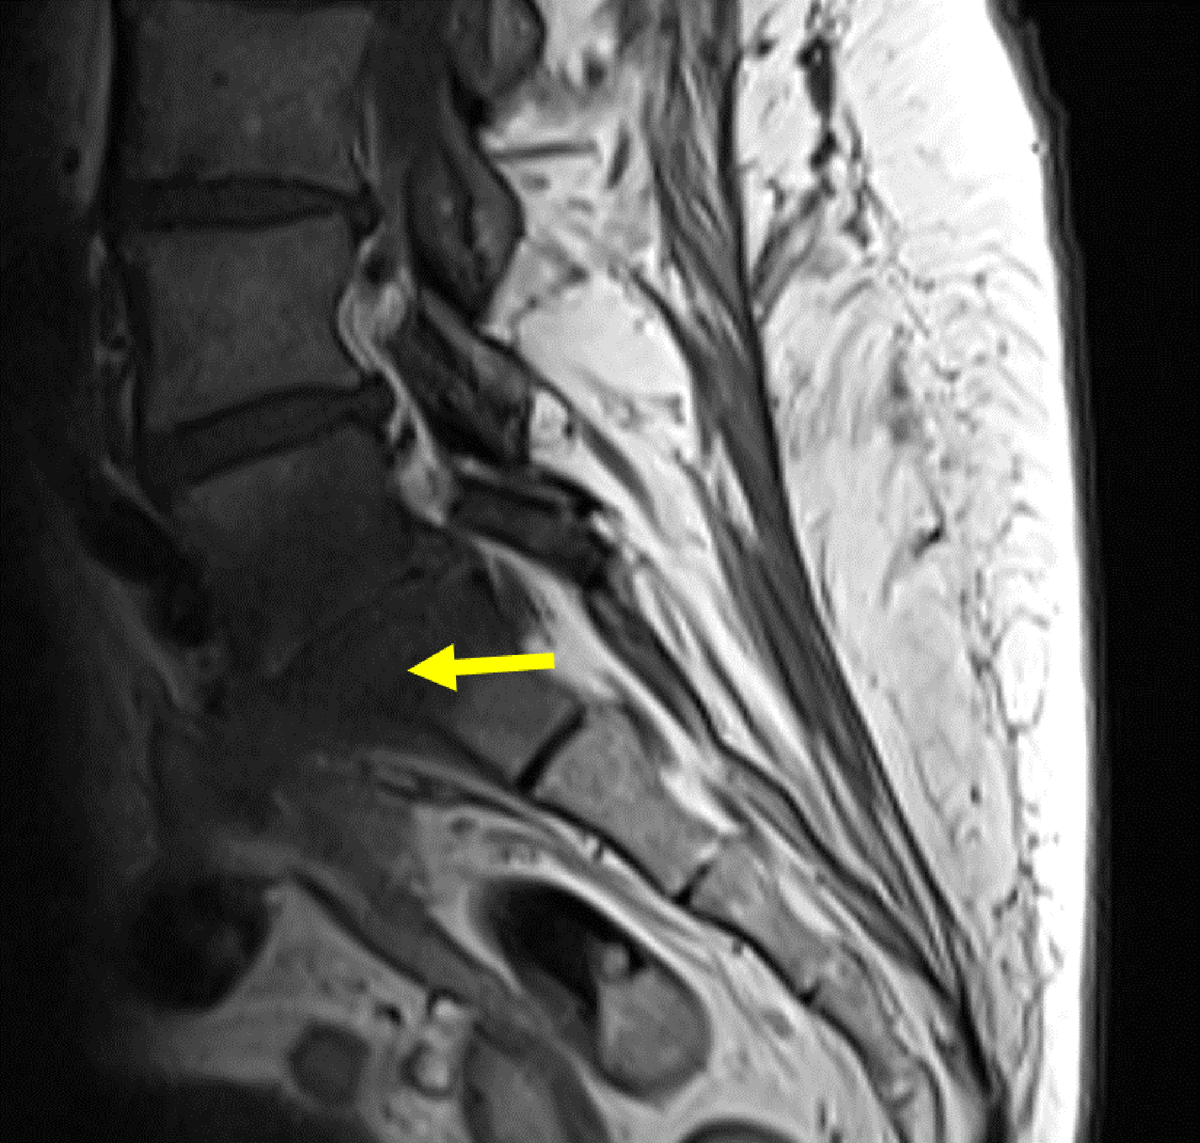

Figure 6

Coronal 3D contrast MRI in T1 fat saturation weighing: Full path of fistula from L5-S1 (yellow arrow) to the vagina (red arrow). The fistula presents with a hyperintense wall surrounding a hypointense lumen.